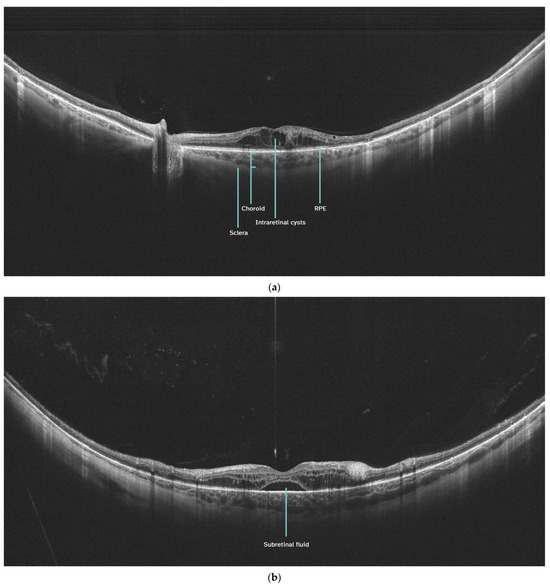

Examples of UWF-OCT scans of patients with DME are presented in Figure 2a,b.

Figure 2. (a). UWF-OCT of significant DME with cystoid changes in the neurosensory retina. The scan engages the optic disc. (b). UWF-OCT of extensive DME with the presence of subretinal fluid. RPE—retinal pigment epithelium.